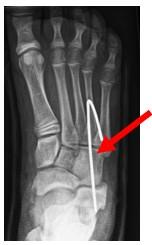

Figuur 4: Röntgenfoto van de voet waarbij we zien dat de K draad (De witte lijn aan het einde vd pijl) in het CC gewrichtje is geplaatst.